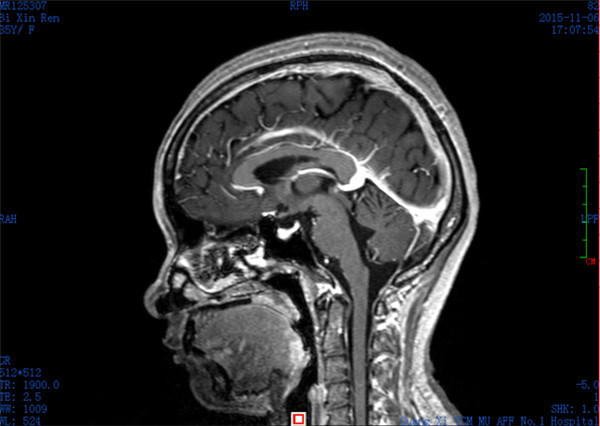

入院CT:脑弥漫点状出血

患者闭某,女性,35岁,因产后十余天,进行性头痛就诊收入我科,患者头颅CT证实颅内多发出血灶,静脉窦栓塞可能。患者入院后头痛呈进行性加重,出现反复癫痫,病情危重。我科张高炼主任医师、黄建荣副主任医师查看病人后认为患者属于上矢状窦栓塞,是急性脑卒中的一类,而且已出现梗塞性出血,保守治疗效果极差,既往无血管内治疗的情况下死亡率高达80%以上,即使存活患者也会有严重的神经功能障碍甚至长期昏迷可能,如进病情一步发展,患者势必因颅内高压、梗塞性出血,甚至引起脑疝而导致死亡。

经与患者及家属充分沟通并获得同意后,外六科脑血管病介入治疗团队立即为患者行全脑血管造影,造影结果证实上矢状窦血栓形成,整个上矢状窦完全闭塞,若不采取措施病情很快就会恶化。再次征得家属同意后果断采取微导管介入手术治疗,手术在起病后当晚开始,由于患者血栓位置深在,需要经动、静脉双重途径置管,技术难度较大。术者选取Solitaire支架( 美国 公司)置入微导管远端,释放支架并在原位作短暂停留使支架与血栓充分接触并黏附,一起回撤支架与微导管取出血栓,手术一直持续到第二天凌晨。术后留置导管一条,用于每天以药物继续溶栓。术后患者即清醒,头痛明显缓解,无神经功能缺失。手术第二周时患者已经能够生活自理。2015年12月12日患者痊愈出院。